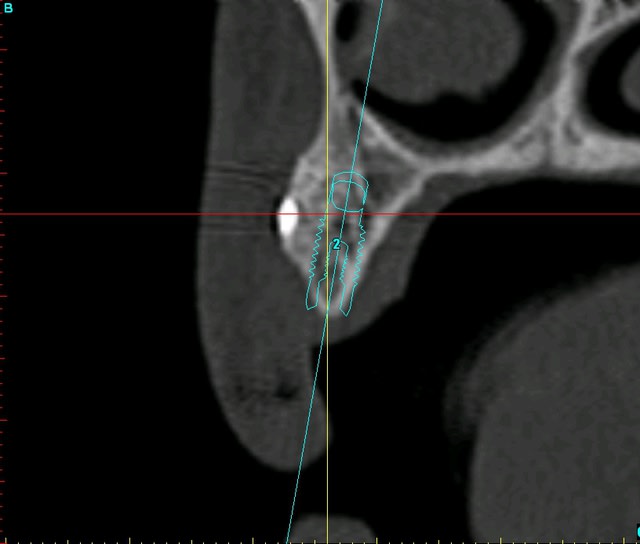

je vous remets les images avant/après pour un comparo...;-)

Planif euc3aq - Eugenol

Plan c8bcsp - Eugenol